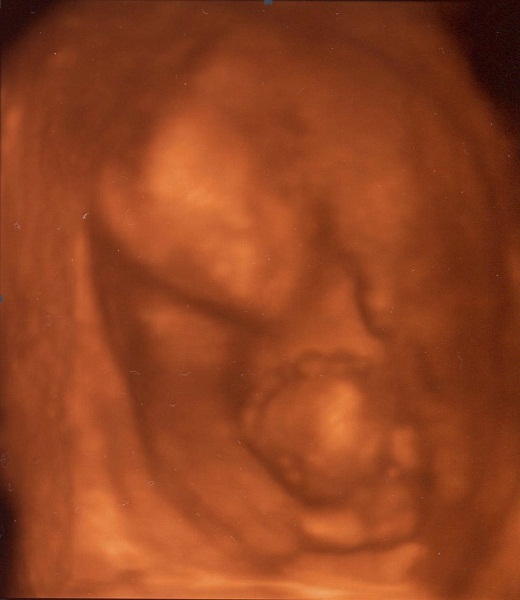

Kicsi bújós Luca babánk